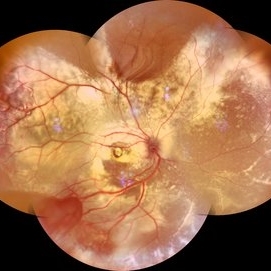

Von Hippel-Lindau Syndrome

Color photo montage of a 19-year-old female with Von-Hippel-Lindau syndrome.

Photographer: Dr. Akansha Sharma-Retina Foundation, Ahmedabad

Condition/keywords: angioma, Von Hippel-Lindau